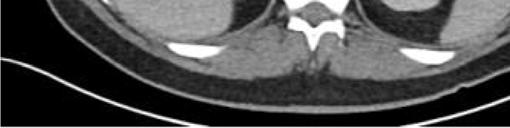

Oninitialevaluation,vitalsignswerenormalexceptfor sinustachycardiaat105beatsperminute.Hewasinmild distresswithmoderatetendernesstopalpationintheleftupper quadrant.Therewasnoguarding,rebound,orrigidity. Laboratoryevaluationshowedawhitebloodcellcountof 21.7 × 103 cellspercubicmillimeter(mm3)(referencerange 4.5 11 × 103 cells/mm3)withaneutrophilpredominanceof 18.9 × 103 cells/mm3 (2 7.8 × 103 cells/mm3)andanelevated bloodureanitrogenat25milligrams(mg)/deciliter(dL) (9–20mg/dL).Thepatient’selectrolytes,liverfunction tests,andserumcreatininewerewithinnormallimits. Acomputedtomography(CT)oftheabdomenandpelviswith intravenouscontrastwasorderedtoassessforbowel obstruction,perforation,andballoonintegrity.TheCT indicatedintraluminalgastricballoonwithanteriorgastricwall perforationwithoutevidenceofintestinalpathology(Image).

GeneralsurgerywasconsultedandobtainedaCT abdomenandpelviswithoralcontrast,whichdirectly showedextravasationintotheperitonealcavity.Thepatient wasemergentlytakentotheoperatingroomforan exploratorylaparotomy,abdominalwashout,removalofthe IGB,andgastricperforationrepair.Hewasstartedon piperacillin/tazobactamand fluconazoleforpurulent peritonitis.Afteranovernightstayinthesurgicalintensive careunit,hewastransferredtothesurgical floorwherehe remainedforthefollowing10days.Onday5,afollow-up uppergastrointestinalserieswithgastrografinwasobtained, andnocontrastextravasationwasnoted.Thepatient’sdiet wasadvanced,andhewasdischargedonpostoperativeday 10withamoxicillin-clavulanatefor10days.Forty-twodays afterdischargethepatientwasnotedtoberecoveringwellon afollowupvisit.